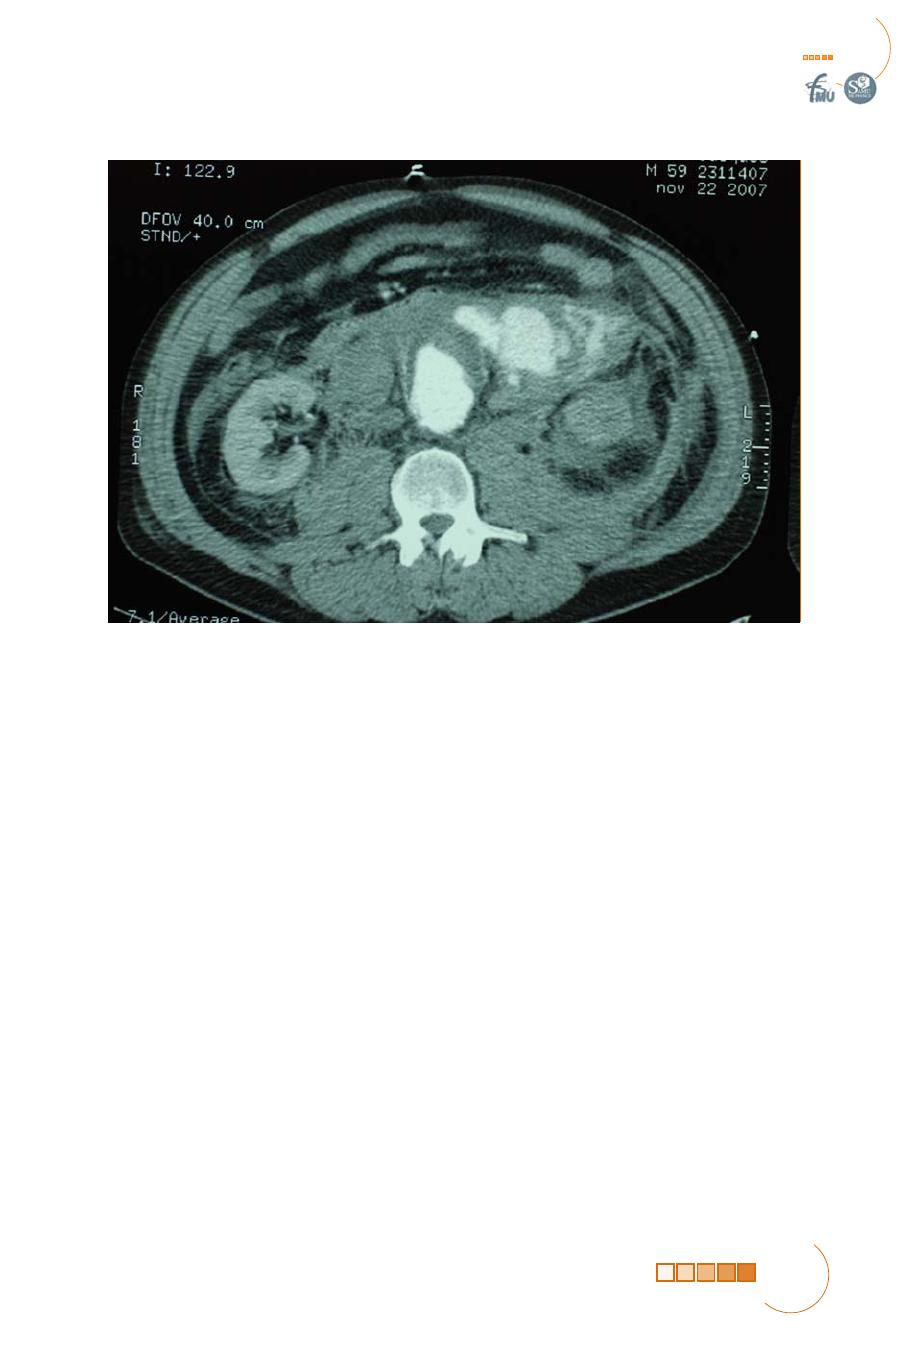

ANÉVRYSME AORTIQUE ABDOMINAL FISSURÉ OU ROMPU

Les douleurs abdominales et le collapsus sont les manifestations cliniques les plus

fréquentes de la rupture des AAA. Les douleurs peuvent être épigastriques ou

péri-ombilicales, elles peuvent également siéger au niveau des flancs ou des lom-

bes. Des irradiations vers l’aine sont fréquentes, ce qui peut faire évoquer à tort

le diagnostic de colique néphrétique. La douleur est intense, profonde et conti-

nue. Elle résiste aux antalgiques simples qui ont parfois été prescrits au début

des douleurs. Le collapsus peut être plus ou moins profond et dépend de

l’importance de la perte sanguine mais aussi de l’intensité de la réaction végé-

tative aux douleurs. L’association de ces symptômes à une masse abdominale

battante doit faire évoquer le diagnostic mais elle n’est présente que dans 60 %

des cas environ

(4)

. L’examen clinique peut être très difficile en raison de la dis-

tension abdominale et de l’importance des douleurs. Le diagnostic est facilité si

l’anévrysme était connu du patient, de sa famille ou de son médecin traitant.